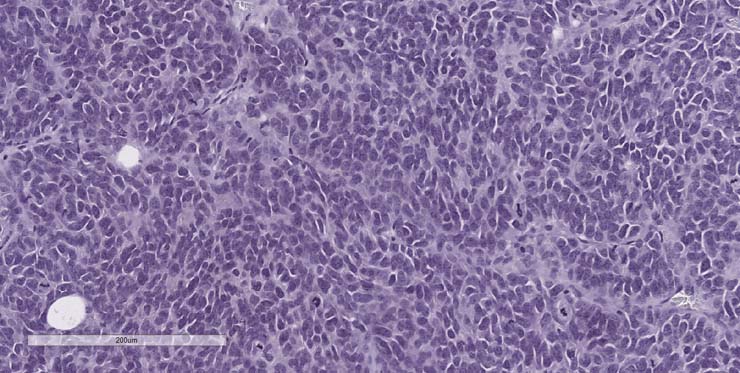

P1 pathology consistent with a metastatic and highly treated Ewings Sarcoma with aberrant cytokeratin expression. P2 Pathology consistent with Ewings Sarcoma.

P2 tumor ID011 for PDX model J000109079 stained for H&E.